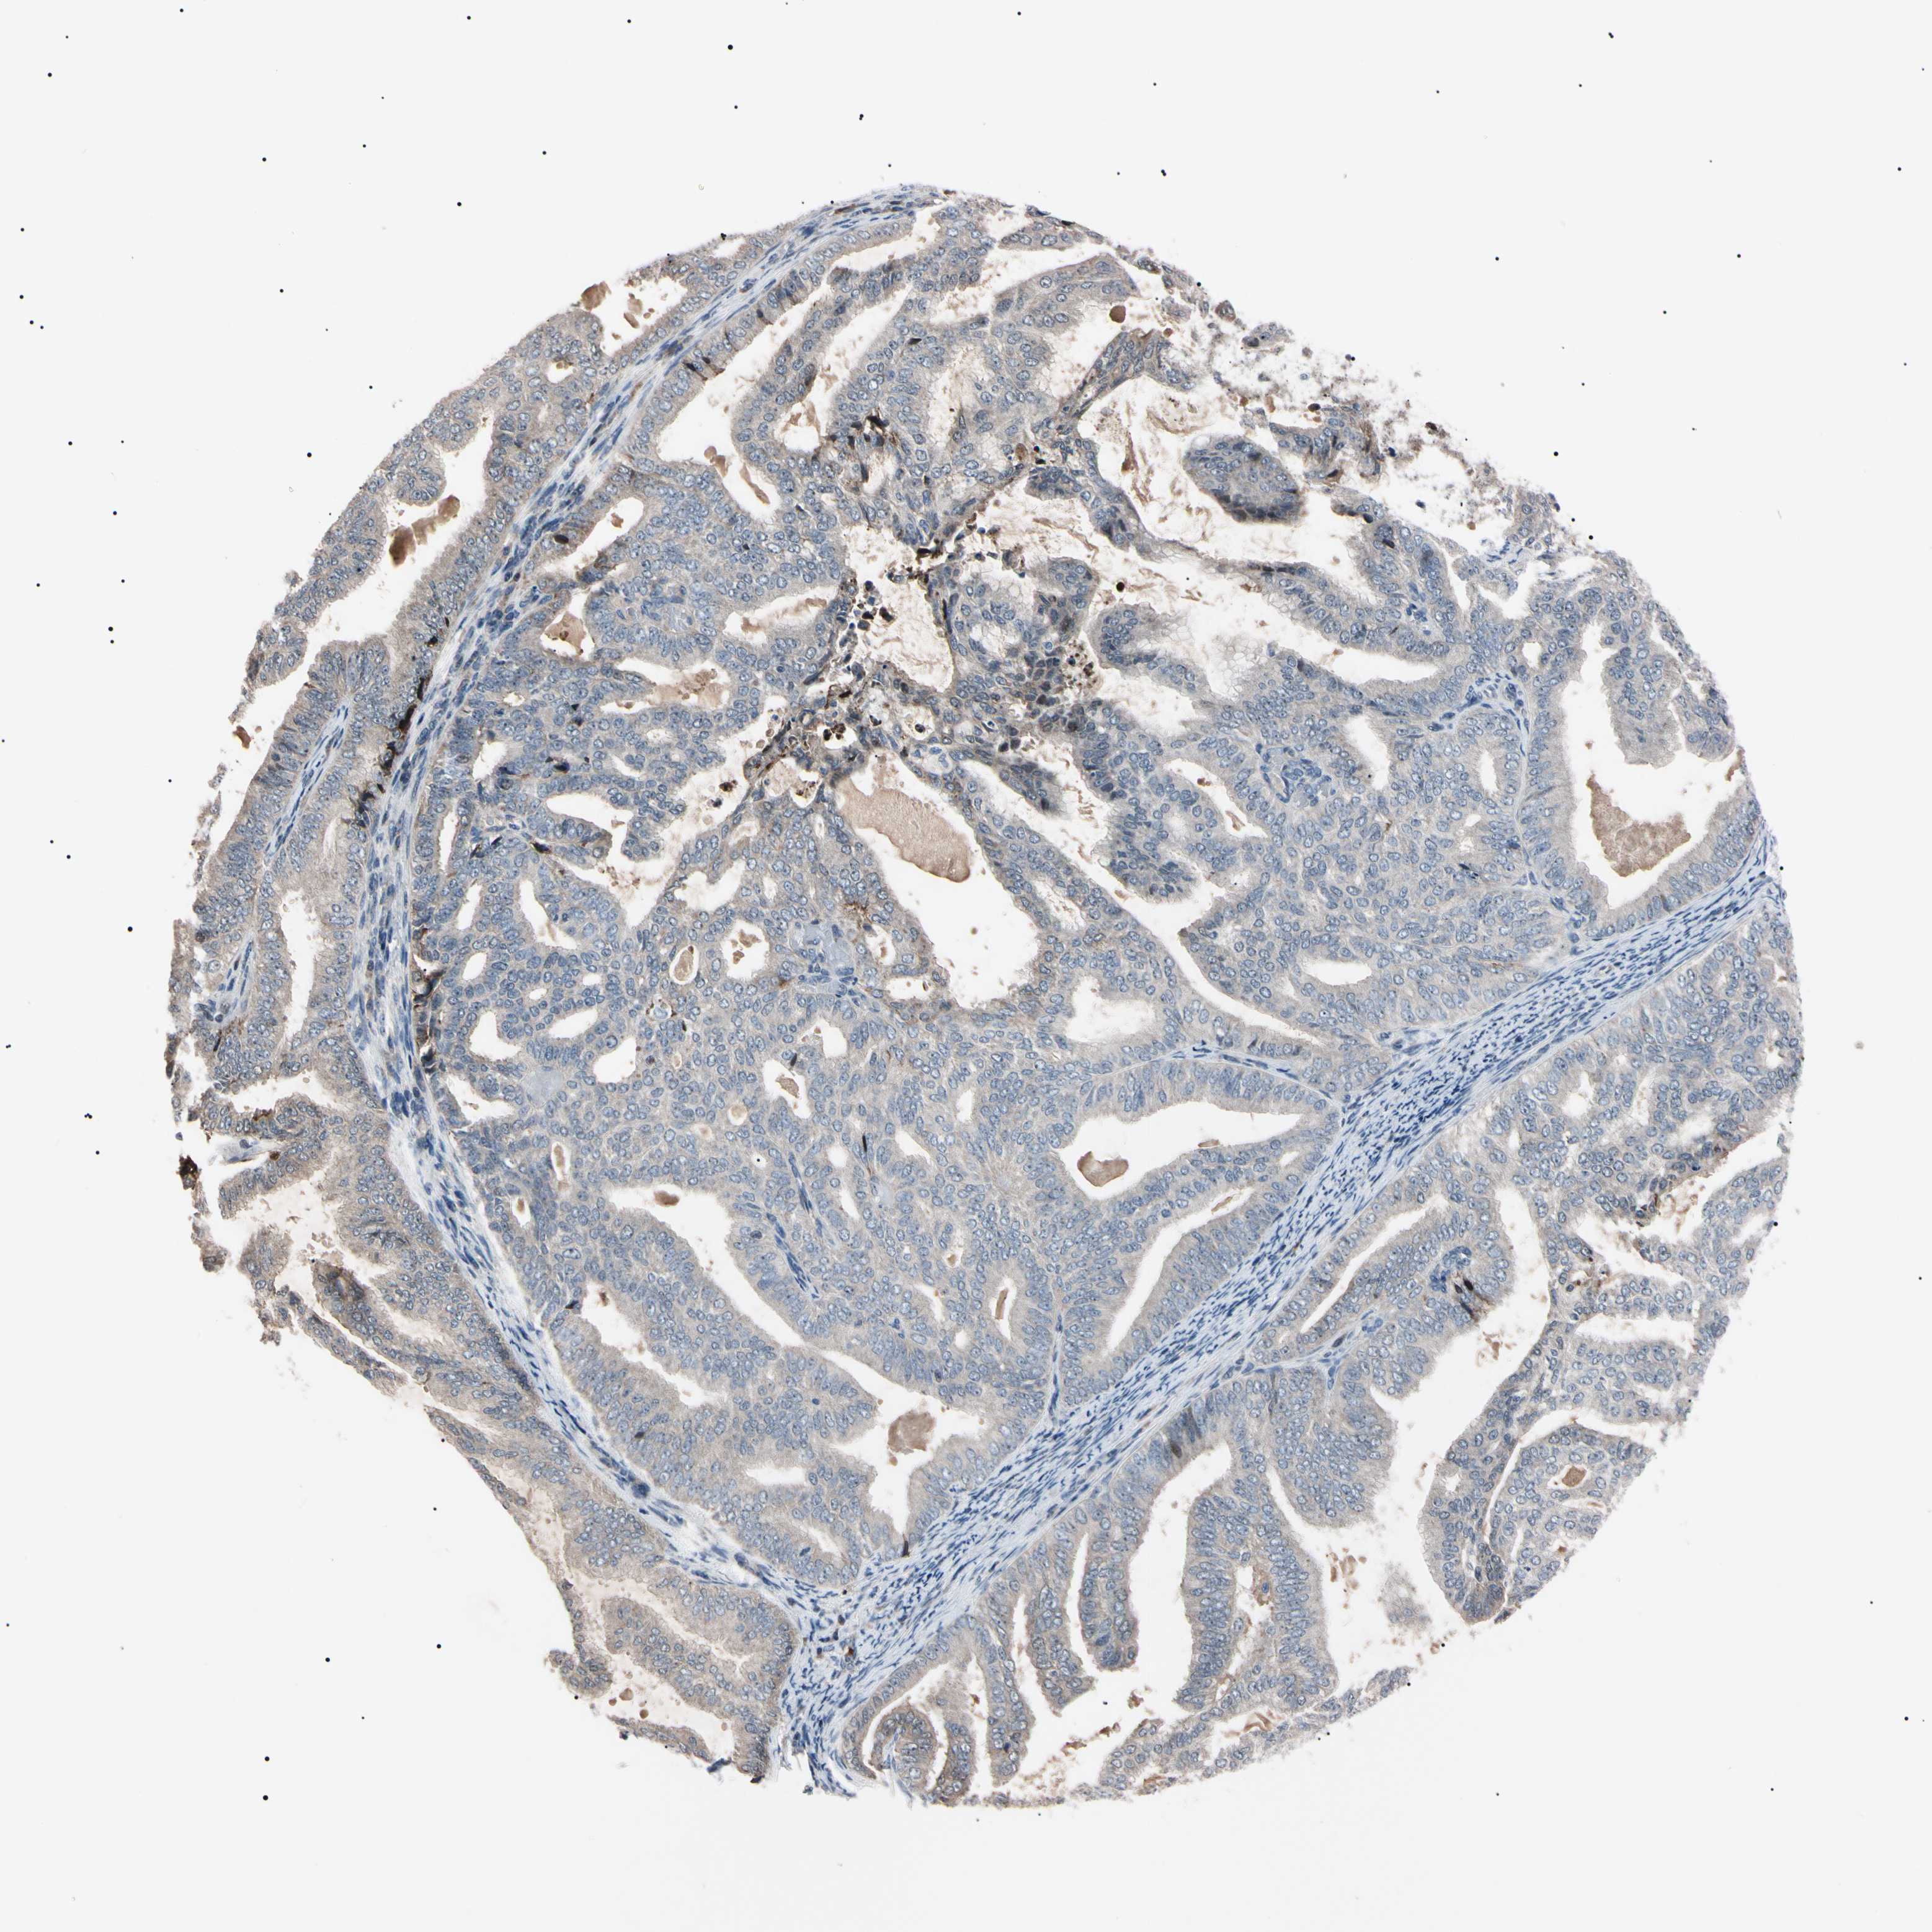

ENDOMETRIAL CANCER - Protein expressioni

A mouse-over function shows sample information and annotation data. Click on an image to view it in a full screen mode. Samples can be filtered based on level of antibody staining by selecting one or several of the following categories: high, medium, low and not detected. The assay and annotation is described here.

Note that samples used for immunohistochemistry by the Human Protein Atlas do not correspond to samples in the TCGA dataset.

Antibody stainingi

Antibody staining in the annotated cell types in the current human tissue is reported as not detected, low, medium, or high, based on conventional immunohistochemistry profiling in selected tissues. This score is based on the combination of the staining intensity and fraction of stained cells.

Each image is clickable and will lead to virtual microscopy that enables deeper exploration of all samples and also displays staining intensity scores, fraction scores and subcellular localization as well as patient and tissue information for each sample.

Antibody HPA008052

Antibody CAB010277

Staining

High

Medium

Low

Not detected

Intensity

Strong

Moderate

Weak

Negative

Quantity

>75%

75%-25%

<25%

None

Location

Nuclear

Cytoplasmic/membranous

Cytoplasmic/membranous,nuclear

Adenocarcinoma, NOS